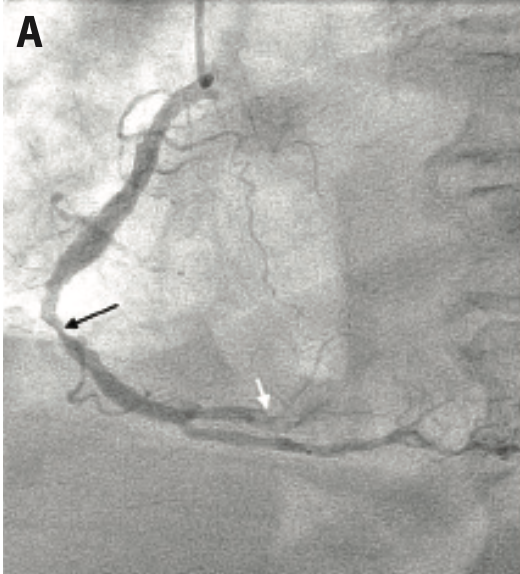

A 67-year-old male with a history of type II diabetes mellitus and hypertension transferred from the outlying facility due to confusion and mid epigastric pain of two days duration. Vital signs were notable for blood pressure 156/77 mmHg and a heart rate of 110 beats per minute. Physical examination was unremarkable except for tachycardia, diminished breath sounds in the lower lung fields, and bilateral lower extremity pitting edema. The patient’s lab workup revealed an elevated white blood count of 31.3 K/µL (reference range: 4.0-11.0 K/µL) with bands, elevated troponin of 9.53 ng/mL (reference range: 0.00-0.03 ng/mL), brain natriuretic peptide (BNP) of 1563 pg/mL (reference range: 0-100 pg/mL) and creatinine of 1.85 mg/dL (reference range: 0.50-1.30 mg/dL). An electrocardiogram showed sinus tachycardia with 1 mm ST-segment depression in leads I, V4, and V5. Echocardiogram showed an ejection fraction of 50-55% without regional wall motion abnormalities. He was admitted with a diagnosis of sepsis with hypotension, Hemophilus influenzae pneumonia, and lower extremity cellulitis. The patient was in respiratory failure and required intubation. Five days after the patient improved, a coronary angiogram was performed through right radial access, revealing a mid right coronary artery (RCA) calcified 80% stenosis and an acute thrombotic occlusion of the right posterolateral (rPL) artery with TIMI 0 to 1 flow (Figure 1A-B). The left coronary system showed a patent left main coronary artery, 30% distal left anterior descending artery stenosis, 70% mid left circumflex artery stenosis, 99% proximal total occlusion of the 1st obtuse marginal (OM), and 99% mid total occlusion of the 2nd OM.